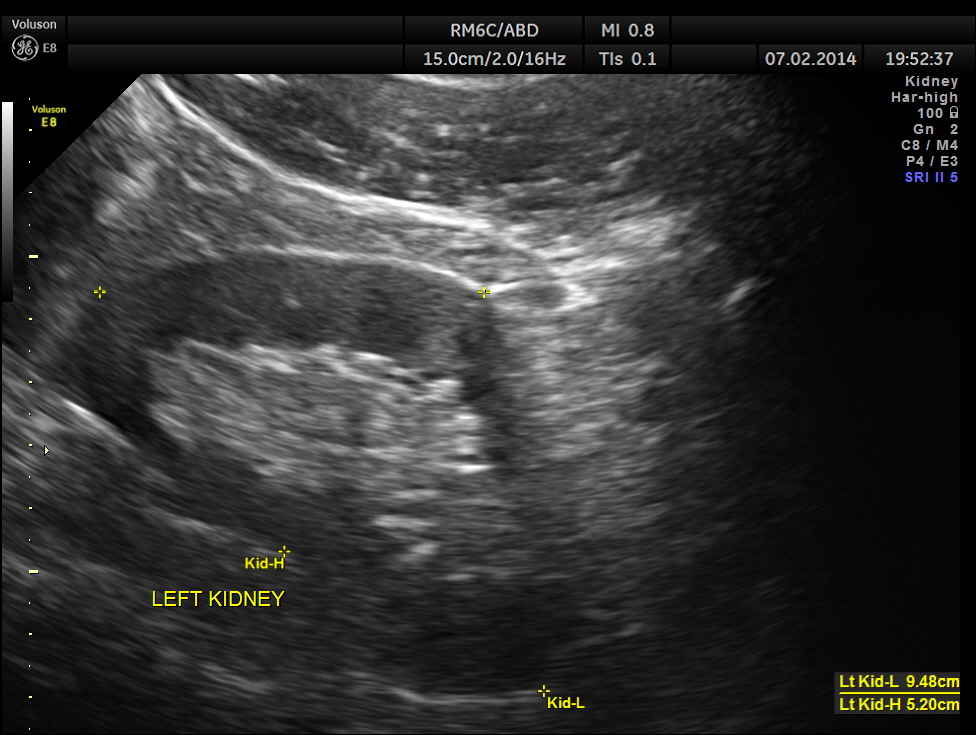

The following pictures show the testicles.Mild left hydrocele is also seen.

The kidneys appeared normal.